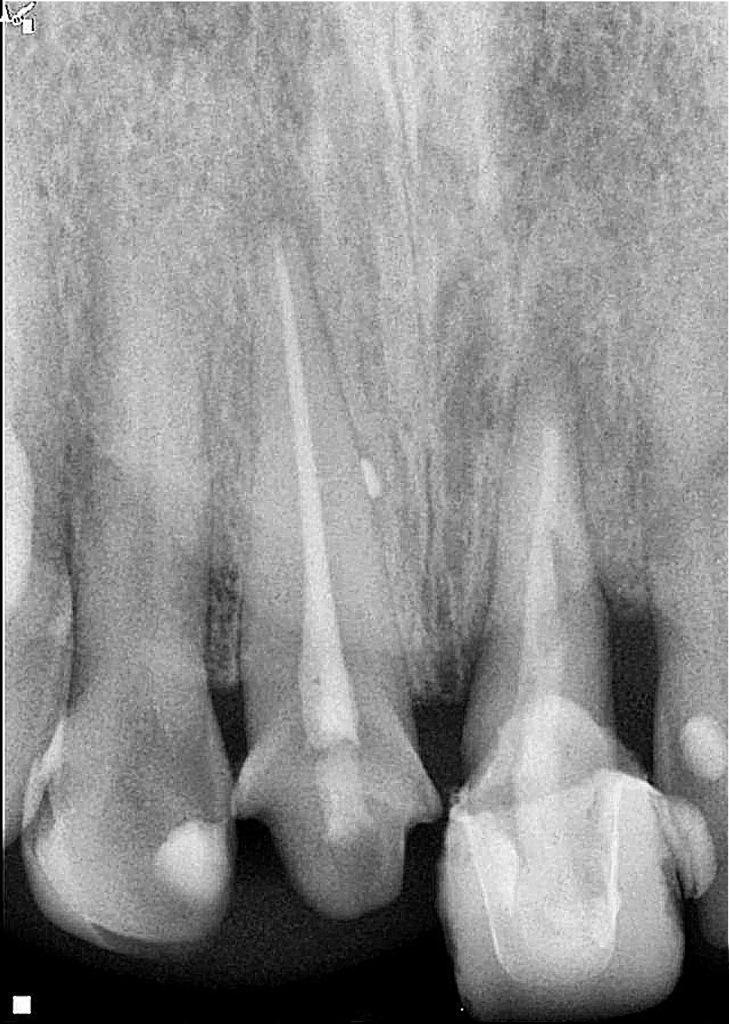

У пациентки случилась травма зубов верхней челюсти. У нее был косой перелом от мезиальной до дистальной части левого центрального резца верхней челюсти на поддесневом уровне. Штифт и металлокерамическая коронка были подвижны. Периапикальная ткань зуба была здоровой (фото 1). При рентгенологическом и клиническом обследовании было отмечено, что структура зубов недостаточна для предсказуемого восстановления. Планирование лечения включало измерение и анализ длины корня, ширины стенок корневого канала и имеющейся наддесневой структуры. Для сохранения зуба были рассмотрены различные варианты лечения, и после всесторонней оценки хирургическая экструзия была выбрана в качестве предпочтительного варианта для достижения адекватной здоровой наддесневой структуры зуба, тем самым предлагая пациентке благоприятное долгосрочное решение для лечения.

Фото 1: Первичная клиническая рентгенограмма, на которой показан зуб 21 с предыдущим лечением корневого канала, штифтом, полной коронковой реставрацией и косым переломом от мезиальной к дистальной части.